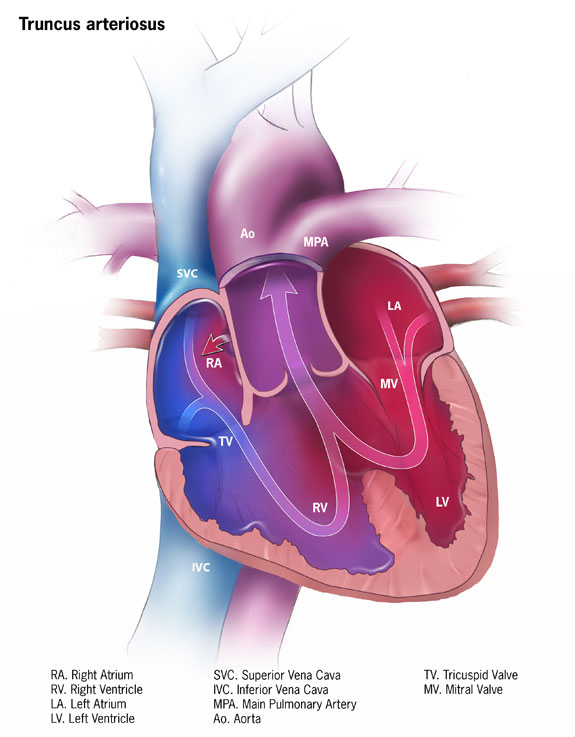

Truncus Arteriosus

Truncus arteriosus is characterized by the emergence of a single, sizable vessel from both ventricles.

Truncus arteriosus is due to a failure of division.

Truncus arteriosus has an early cyanotic presentation.

Before the pulmonary and aortic circulations separate, deoxygenated blood from the right ventricle and oxygenated blood from the left ventricle combine.